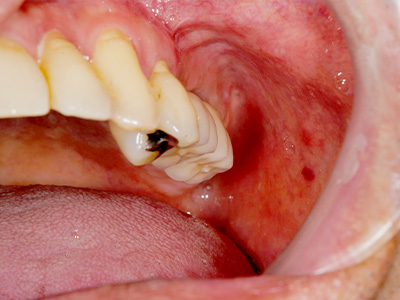

インプラント埋入術後、インプラントが骨に生着したので二次手術を行った後の写真です。

骨吸収の大きかった部位に、きっちり3本のインプラントが植立できました。 -